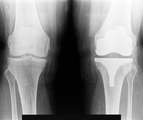

Артрография осуществляется наметить суставы и связки. Краситель вводится в сустав и рентгеновские лучи приняты с целью выявления любых травм.